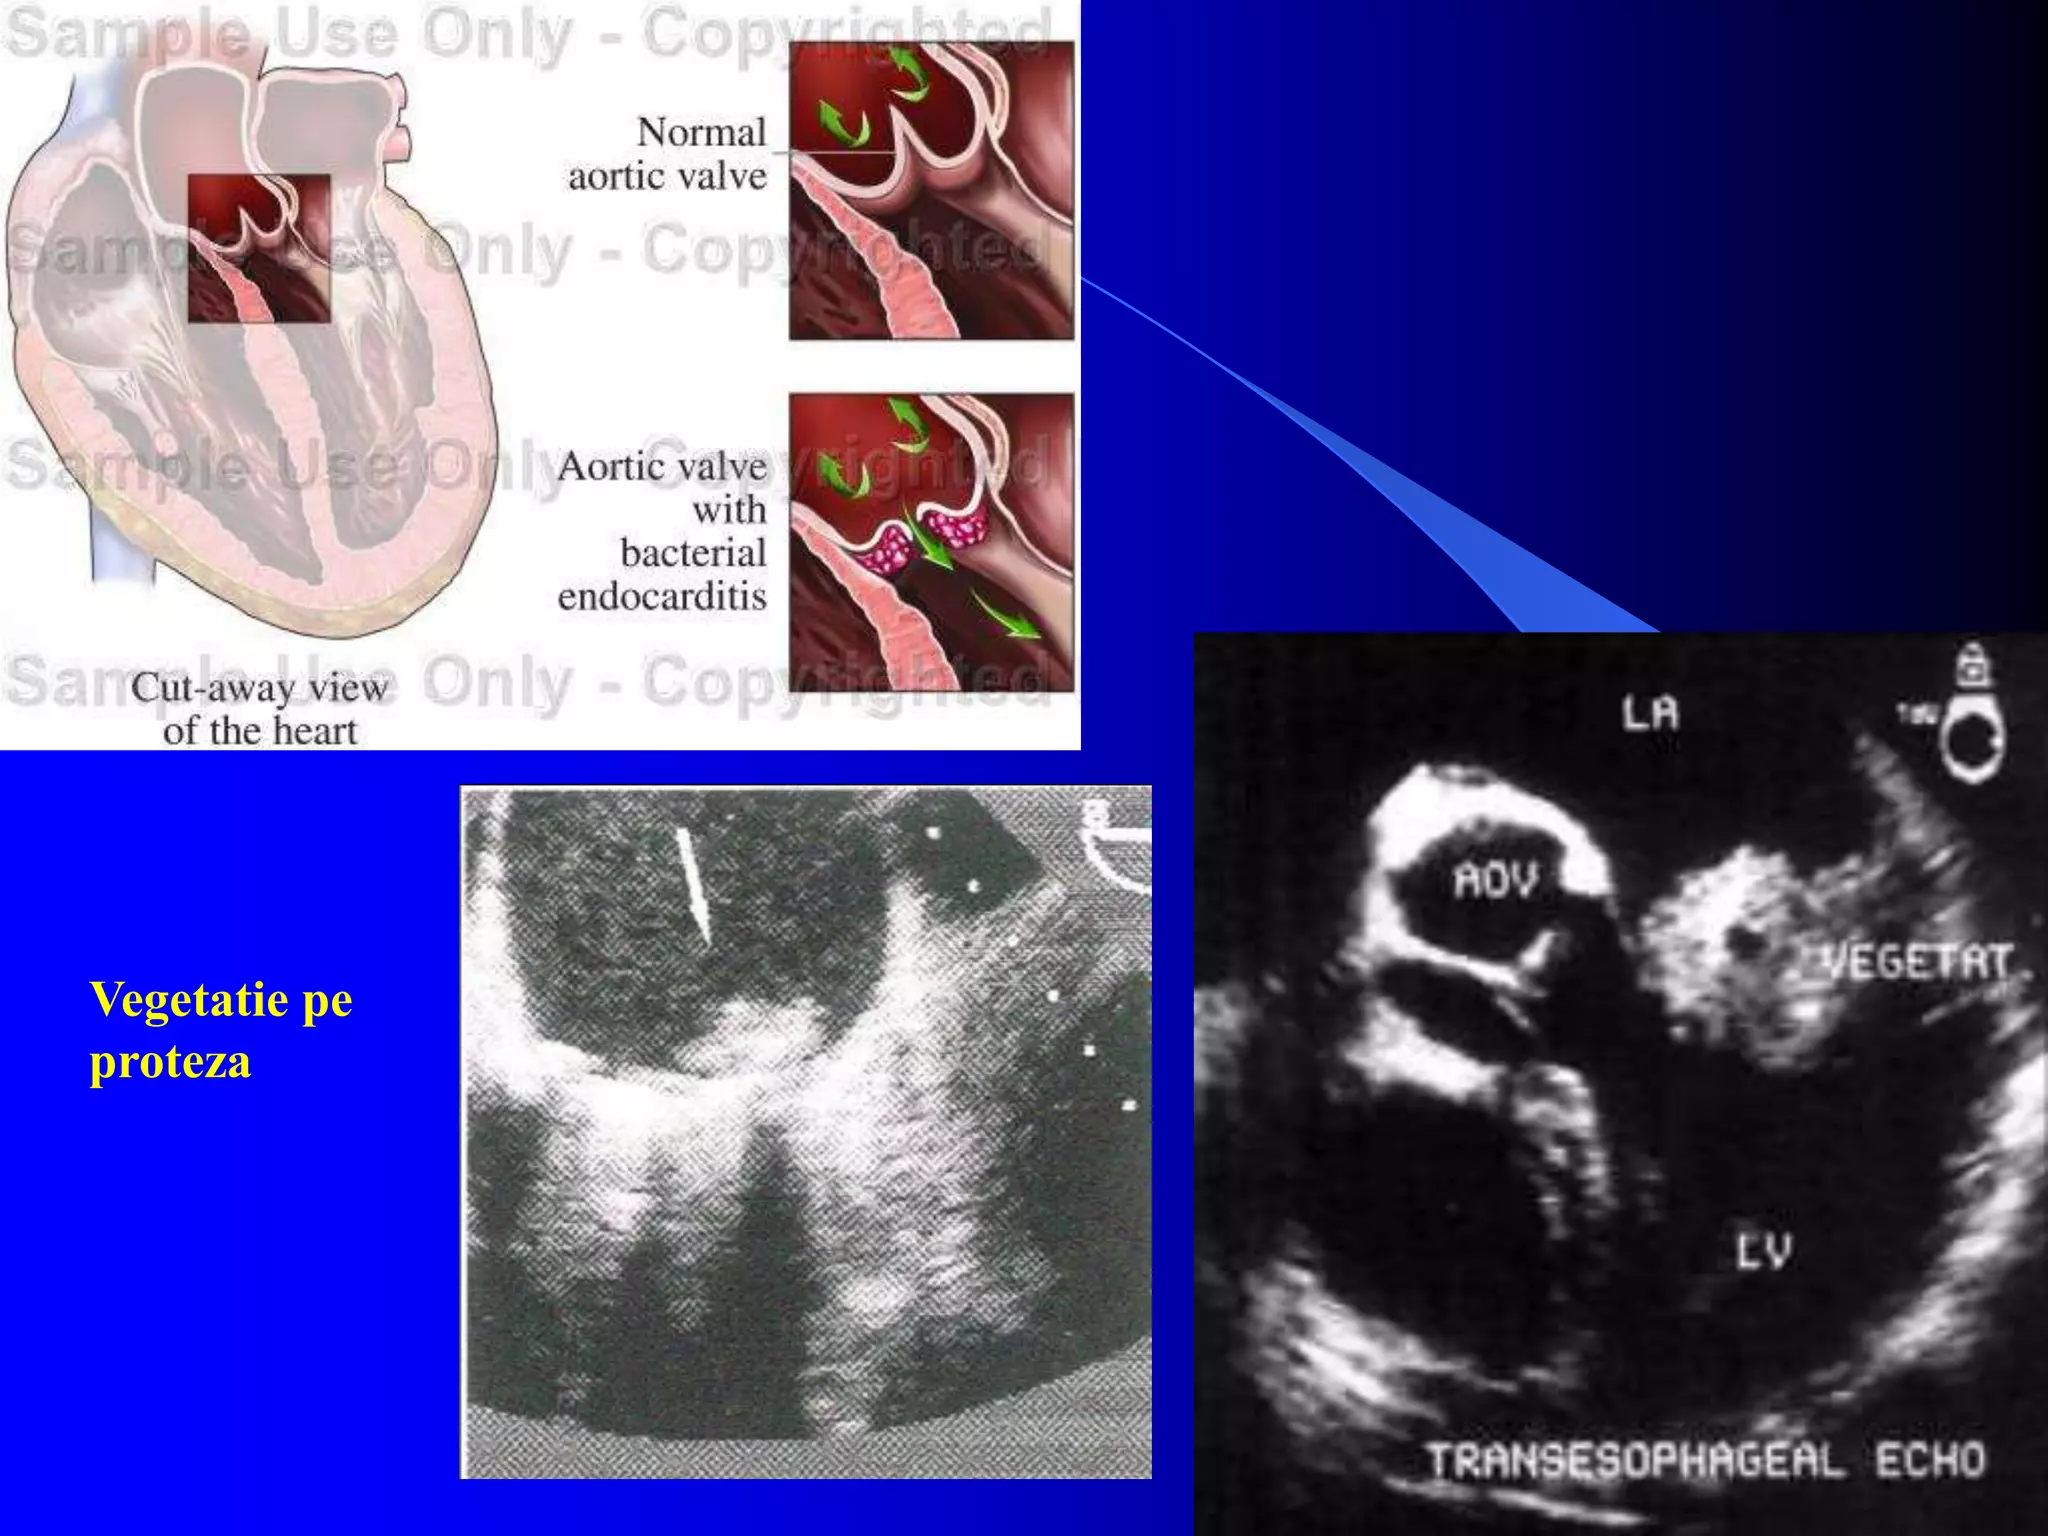

Vegetatie extensiva pe valva aortica

Vegetatii aortice indepartate in vederea

protezarii

Vegetatie pe

proteza

Vegetatie extensiva pevalva aortica Vegetatii aortice indepartate in vederea protezarii